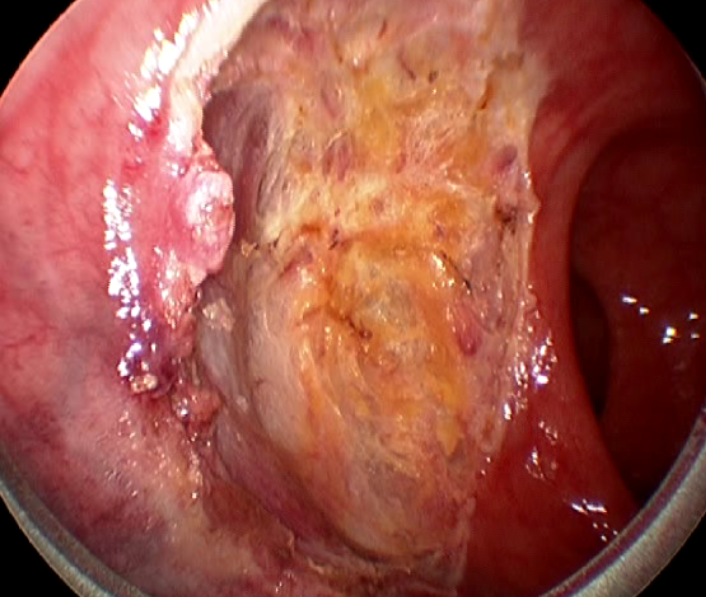

Colorectal cancer affects approximately 1:20 of the population and in South Africa is largely managed by general surgeons. Management of this disease has undergone very significant changes over the last two decades. Until very recently, only two academic general surgery departments included a specialist colorectal unit, and this remains so in the majority of our universities. This has resulted in a generation of surgical graduates who are unfamiliar with, and unskilled in current best management practices for this disease. Rectal cancer is particular challenging and attracts extremely high morbidity and mortality, with poor oncological outcomes. Repeatedly, outcome has been shown to be worse in the hands of generalists, rather than specialist colorectal surgeons, of whom there are very few in the country. This review presents the most important advances of the last 20 years and highlights current controversies and frontiers.